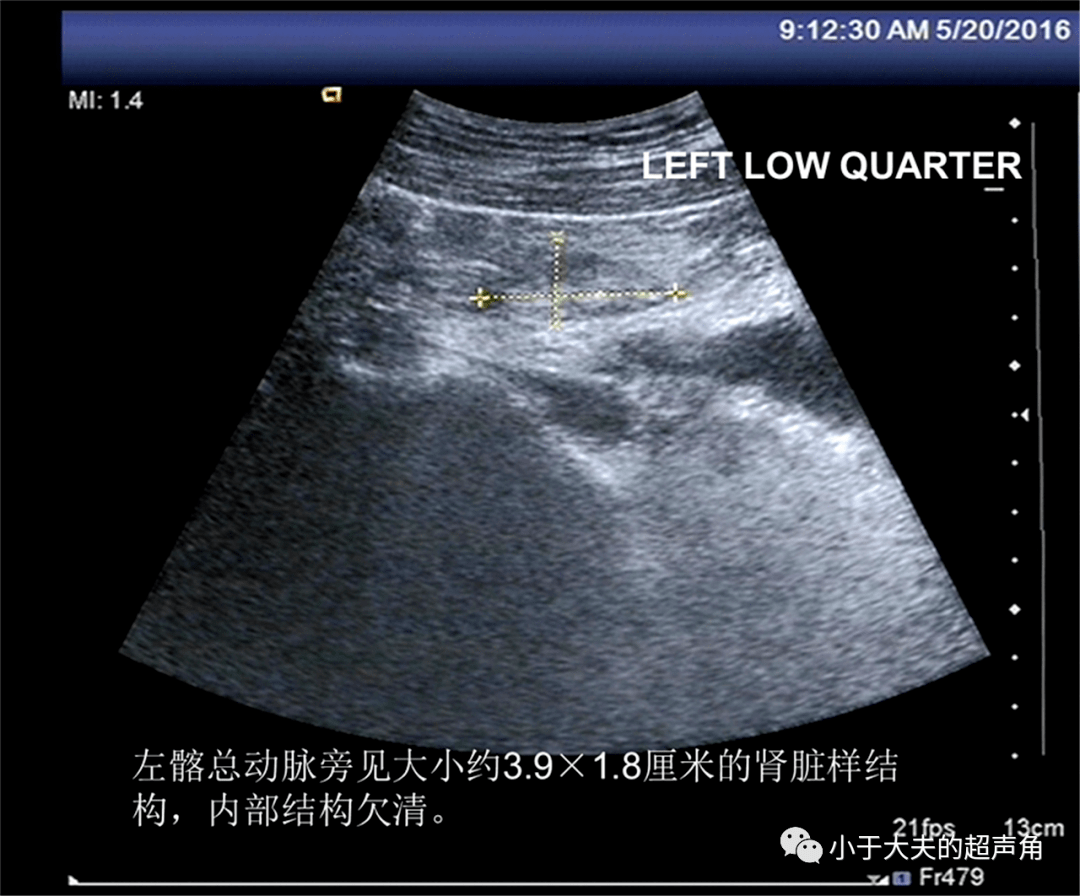

左肾区未探及正常肾脏结构 。 左输尿管扩张 , 较宽处约1.8cm , 扩张长度约10.0cm , 其近端似可见大小约3.9×1.8cm的肾脏样结构 , 内部结构欠清 。

图2-4: 左肾区未见正常肾脏结构 , 但发现左输尿管扩张 , 其近端似可见肾脏样结构 。